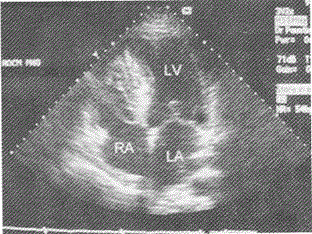

在心尖四腔切面鉴别二尖瓣与三尖瓣,下列正确的是

- B.二尖瓣附着点位置高

- C.三尖瓣附着点位置高

二尖瓣前叶附着点比三尖瓣隔叶的附着点位置高。